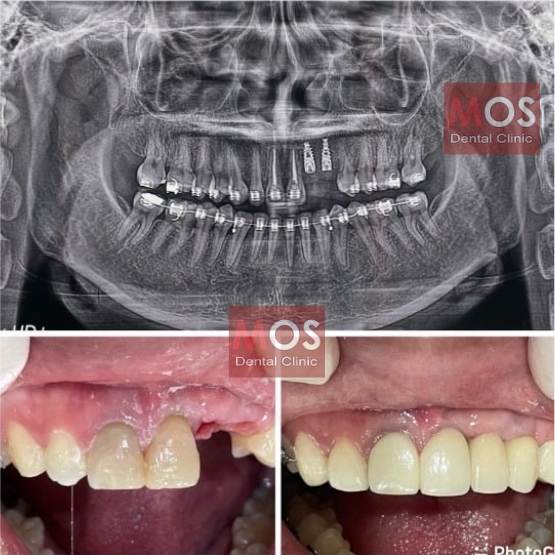

เคสคนไข้รากเทียม 1

เคสคนไข้รากเทียม 2

เคสคนไข้รากเทียมพร้อมฟันปลอม

เคสคนไข้รากเทียม